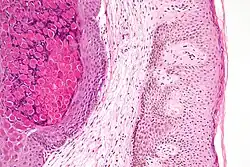

Histologically, molluscum contagiosum is characterized by molluscum bodies in the epidermis, above the stratum basale, which consist of large cells with abundant granular eosinophilic cytoplasm (accumulated virions) and a small peripheral nucleus.[20]

Low magnification micrograph of a molluscum contagiosum lesion -

Low-magnification micrograph of molluscum contagiosum, H&E stain -

High-magnification micrograph of molluscum contagiosum, showing the characteristic molluscum bodies, H&E stain